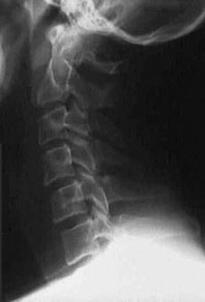

TRAUMA CERVICALA

Incidenta laterala Incidenta

laterala Incidenta

antero-posterioara

Aspect normal Imagine

incompleta Aspect

normal

Incidenta occipitomentala (odontoida)

Aspect normal Incidenta

oblica

Aspect normal

Incidenta oblica Incidenta laterala Incidenta antero-posterioara

Aspect normal Aspect normal Aspect normal